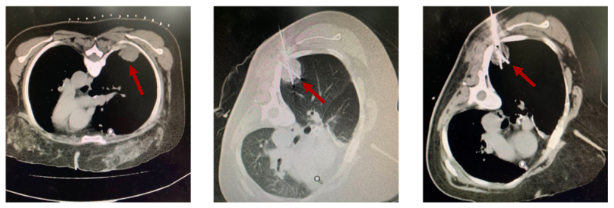

2019-8-15 复查右下肺胸膜下软组织结节较前增大,2019-8-30 程志强教授于CT引导下行右下肺胸膜转移氩氦刀冷冻术。术后2019-9 至今,口服瑞戈非尼80-120mg qd d1-21,q28d,靶向治疗。期间根据患者不良反应分级多次进行靶向药物剂量调整。并辨证给予口服中药,针对靶向治疗不良反应,如手足皮肤反应等,给予外用中药对症治疗。

图4 CT引导下右下肺胸膜转移瘤氩氦刀冷冻消融术